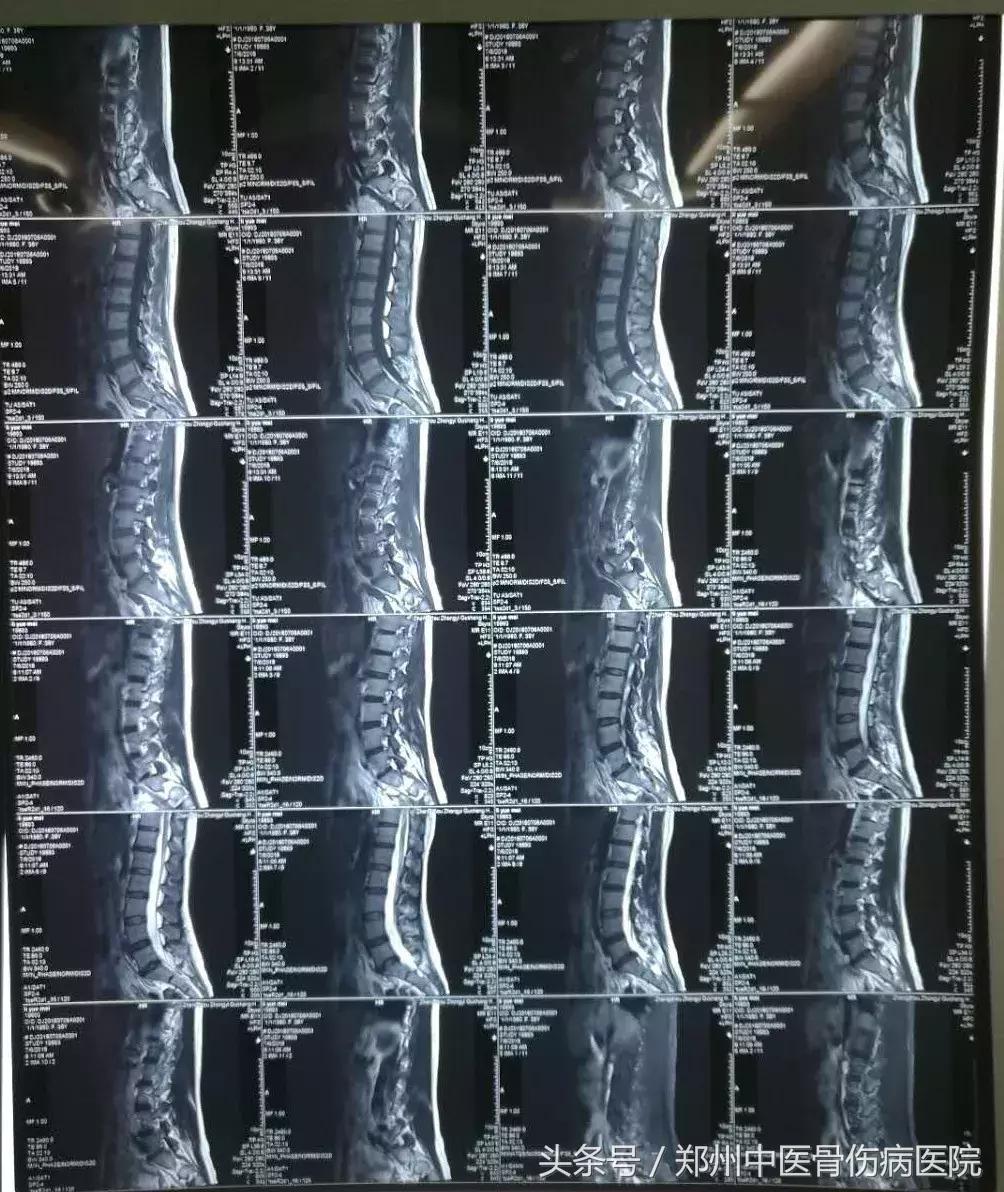

患者周某某,男,43岁、以“腰部疼痛5年加重6月”为主诉来我院就诊,该患者曾在外院多次行按摩、牵引、针灸等治疗,疗效欠佳,来我院后行磁共振检查确诊为腰椎间盘突出症(腰4-5、腰5-骶1)。经过积极的术前准备后,在局麻下行腰椎间盘等离子微创消融术。术程顺利,术后第二天下床活动,疼痛消失,活动自如,术后第六天满意出院。

磁共振显示腰5骶1严重突出